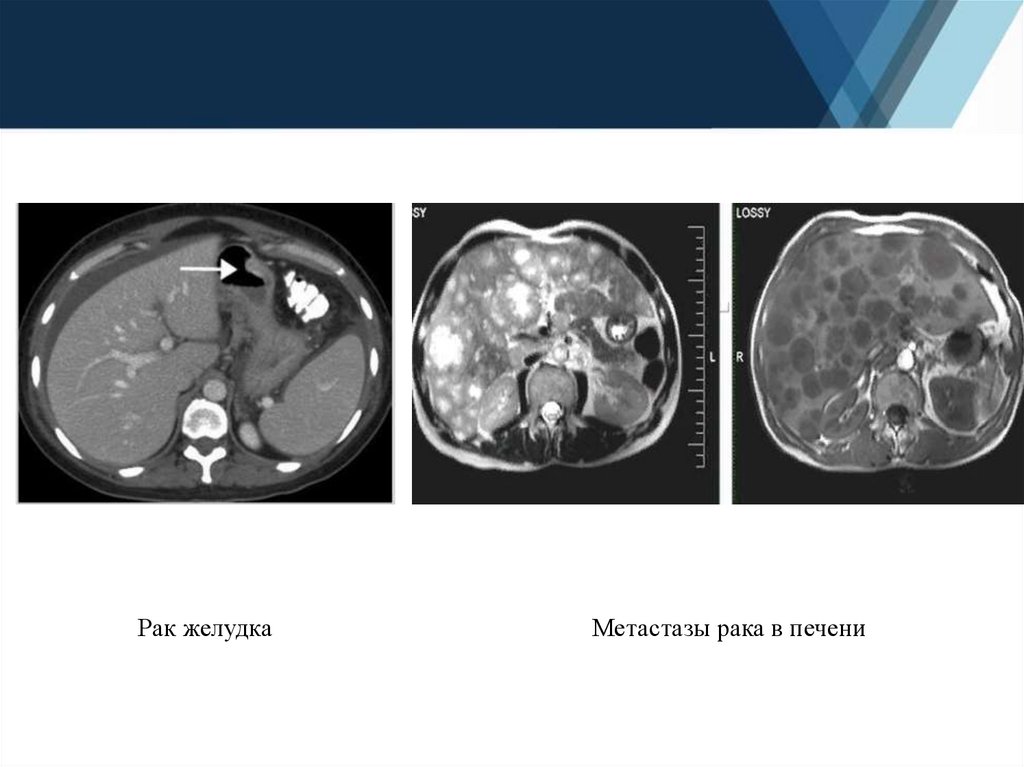

16.

Рак желудка

Метастазы рака в печени